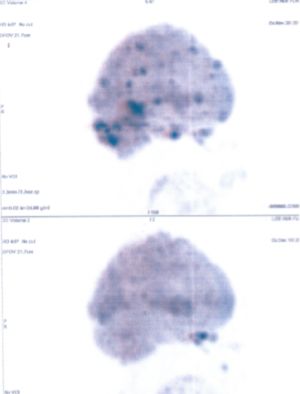

CASE NO: 31 (LUNG CANCER WITH BRAIN METASTASES)

A 40+ woman with lung cancer and brain metastases failed all treatment including radiotherapy and chemotherapy. She cannot walk. After a few treatment, the left lung cancer is gone, and all the brain metastases are gone. She is starting to walk again. One set of pictures shows the left lung cancer, and the other set of pictures show the brain: on top is BEFORE TREATMENT, bottom is AFTER TREATMENT.

CASE NO: 31 AFTER TREATMENT